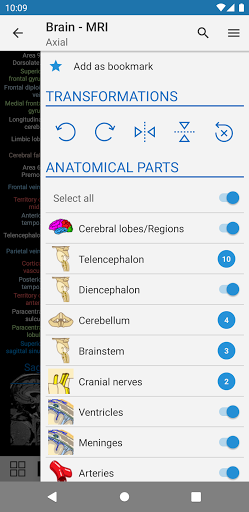

- You can now hide structures one by one (new button inside the description popup) and display them again in the right menu

-Two new modules : Brain - TOF and Brain Angiography, Atlas of normal neurovascular anatomy of arteries of the brain on a cerebral angiogaphy.-The interface has been reworked.-A new tab named "QuickLinks" is available, dispatching modules in sections of the human body and allowing you to fast travel to the modules you are looking for.-Fixed small bugs.